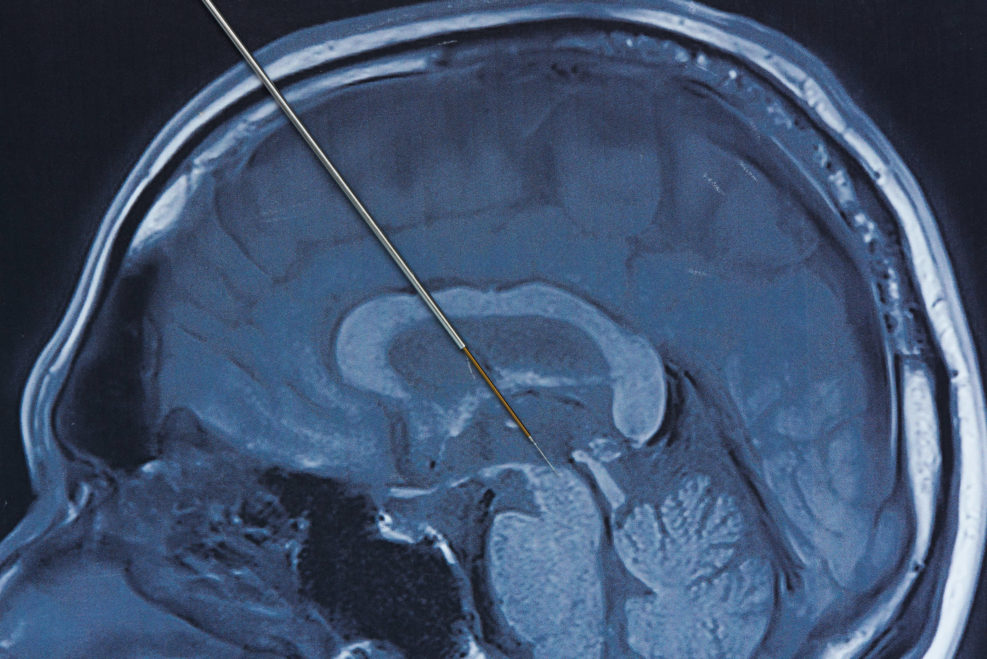

Robert J. Marks: We’re told AI is going to replace lawyers and doctors and accountants and all sorts of people. So, let’s look at a case of the physicians. This was a piece on Mind Matters News. Eric, what do you think? Do you think that AI will ever be better than physicians at diagnosis?

Eric Holloway (pictured): Well, I don’t know if they ultimately will or will not, but right now they definitely are not. This particular author, he took a look at 10 years worth of studies for deep learning algorithms on medical problems, and only two of them actually relied on randomized trials while 81 were not randomized. This means basically people can just pick and choose the type of data that makes their algorithm work well. So, really their results don’t really tell us anything about how well their stuff works in the real world.